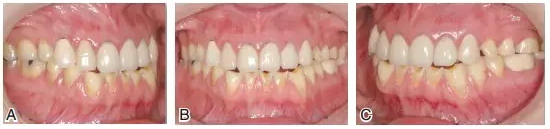

圖7患者J初診時(shí)的下頜前伸(A)及下頜左(B)、右(C)側(cè)方運(yùn)動(dòng)情況??梢娫诰捉肋\(yùn)動(dòng)時(shí),僅有單側(cè)上下頜前磨牙的個(gè)別點(diǎn)接觸,咀嚼效率差,咀嚼肌易疲勞